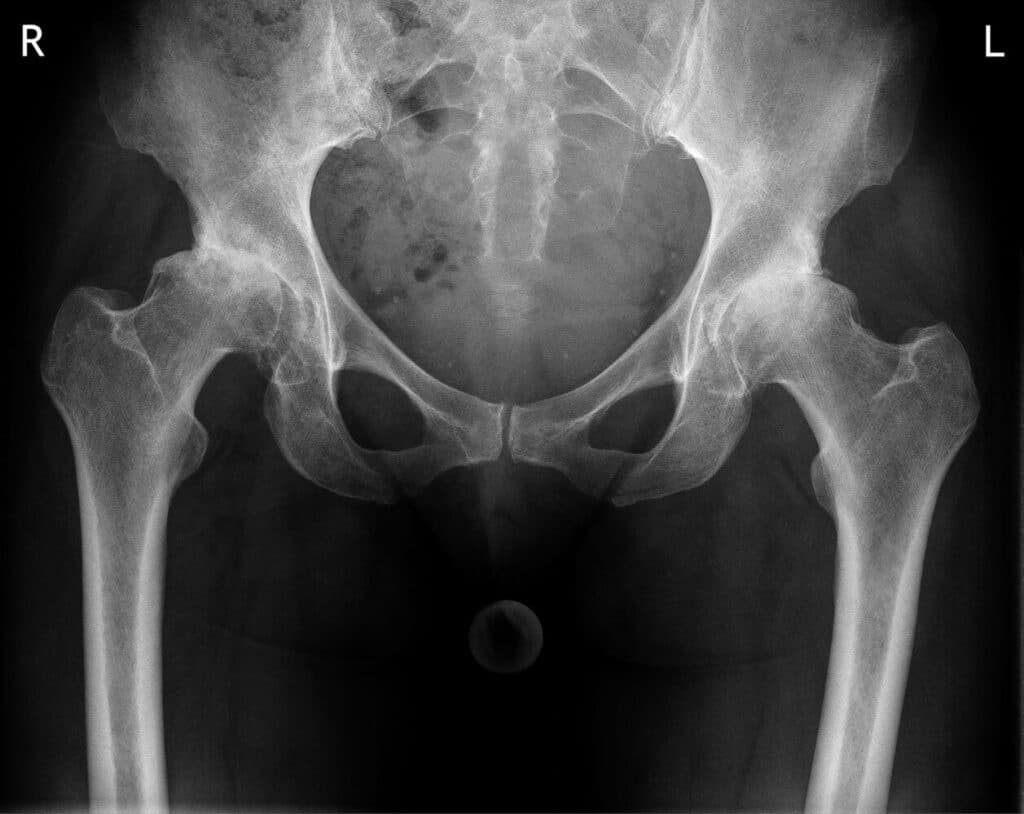

Specijalista fizijatar će na osnovu vaše anamneze i pregleda posumnjati na postojanje koksartroze. Radiografija karlice sa kukovima neophodna je da se potvrdi dijagnoza.

Važno je napomenuti da stepen promene na rendgenskom snimku često nije povezan sa intenzitetom bola koju osoba doživljava. Takođe treba znati da kod većine ljudi njihovi simptomi ostaju slični dugi niz godina i da bolest često napreduje vrlo sporo.Koksartroza

Vredno je ponoviti da mnogi ljudi imaju rendgenske promene koje upućuju na određeni stupanj osteoartritisa, ali nemaju ili imaju vrlo blage simptome.